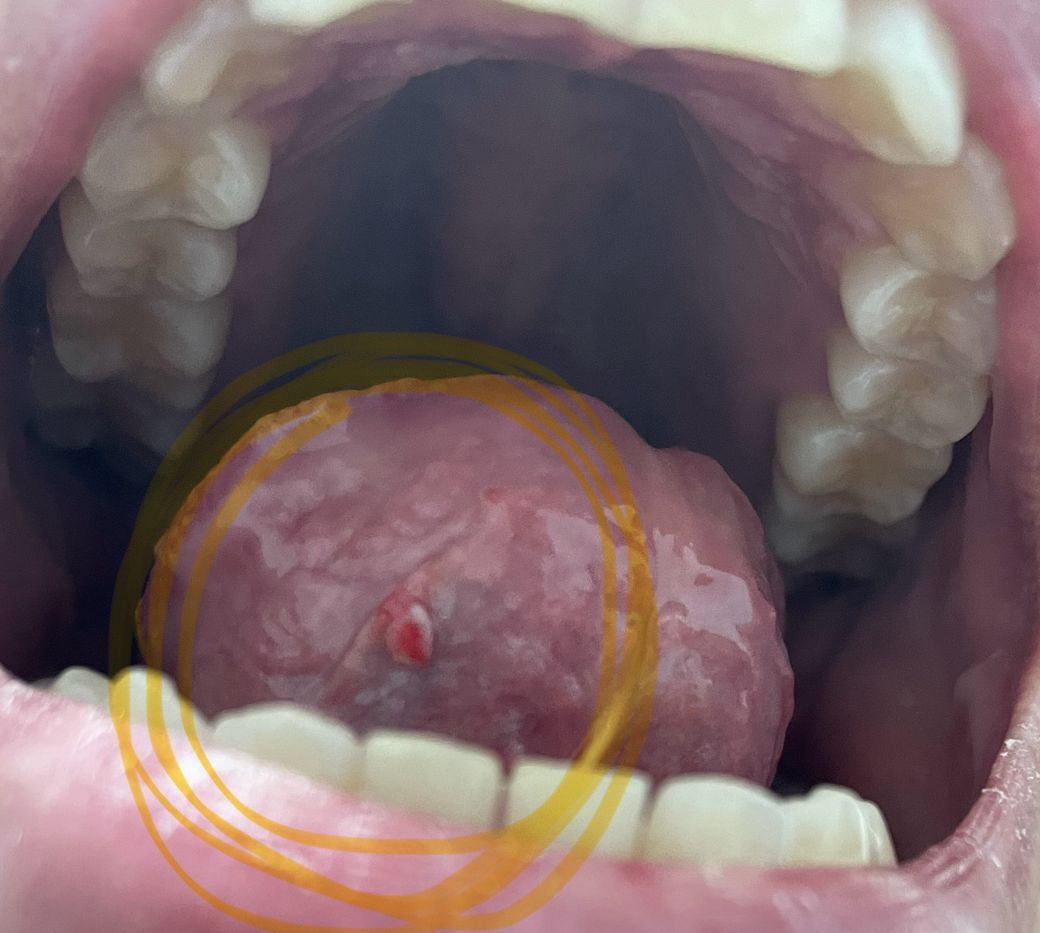

입병처럼 혀가 아파서 보니

혀밑에 이런게 생겼어요

혀를 움직이면서 걸리는 느낌이 나네요

혀밑에 혈종이 발생한 것으로 보이며 이는 염증성 질환으로 악성은 아니지만

증상이 지속되는 경우, 시술을 통해 제거하기도 합니다. 대부분은 치료 없이

호전을 보입니다.